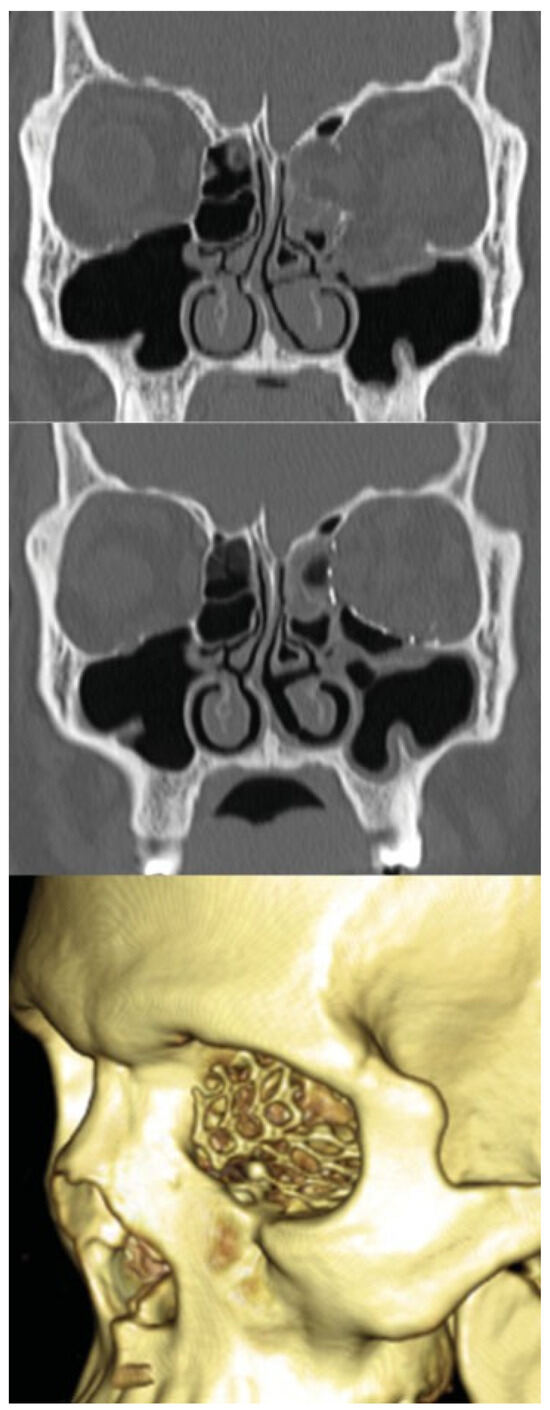

A retrospective chart review was performed encompassing all patients treated by the senior author (A.S.-W.) with a transcaruncular incision for isolated orbital fractures in the Division of Plastic and Reconstructive Surgery and was approved by the Institutional Review Board. The study period comprised 6 years, from June 2007 to June 2013. Data were collected for patient demographics, mechanism of injury, treatment interval, preoperative symptoms, and operative or postoperative complications. Computed tomography (CT) was initially obtained to establish the fracture diagnosis (►Figure 1a); when deemed necessary, postoperative scans were obtained to assess adequacy of reconstruction (►Figure 1b). The fracture areas were calculated from axial, coronal, and sagittal views of the preoperative CT scan.

Figure 1. (a) Available preoperative CT scans and photographs were reviewed for each patient. Top row: A 31-year-old woman sustained right eye injury from assault (top left). Repeat physical exam revealed right-side enophthalmos (2 mm) and hypoglobus (2 mm). Bottom row: CT scan showing medial wall (4.0 cm2) and floor (4.9 cm2) fractures (arrows). (b) Top row: A 31-year-old woman at 10 weeks postoperative follow-up without complaints, enophthalmos, or vertical dystopia after repair of medial wall and floor fractures. Bottom row: Postoperative CT scan and 3D reconstruction showing placement of MEDPOR TITAN.